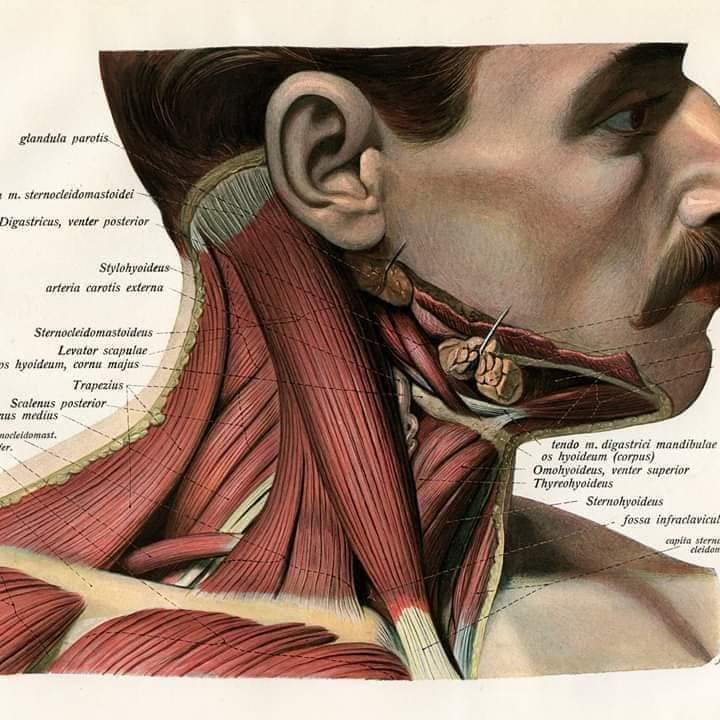

М'язова система людини є однією з основних систем організму, що відповідає за рухи, підтримання пози та стабільність. Вона складається з понад 600 м'язів, які можна класифікувати на скелетні, гладкі та серцеві м'язи. Скелетні м'язи, які є об'єктом нашого детального розгляду, дозволяють контролювати навколишній світ і виконувати різноманітні рухи. Особливу увагу в нашій статті буде приділено шейним і спинним м'язам, оскільки ці групи м'язів мають критичне значення для підтримання правильного постава та функціонування хребта.

Шийні м'язи

Шийні м'язи мають важливе значення для підтримки голови і забезпечення її рухів.

М'язи бічної групи

М'язи, що повертають голову: Стерноклейдомастоїдний м'яз: один з найважливіших м'язів, який дозволяє здійснювати повороти і нахили голови. Він походить від грудини та ключиці і прикріплюється до соскоподібного відростка скроневої кістки.

М'язи, що розширюють шию: М'язи, що розширюють шию: включають трапецієподібний м'яз, який бере участь у піднятті плечей і розширенні шиї.